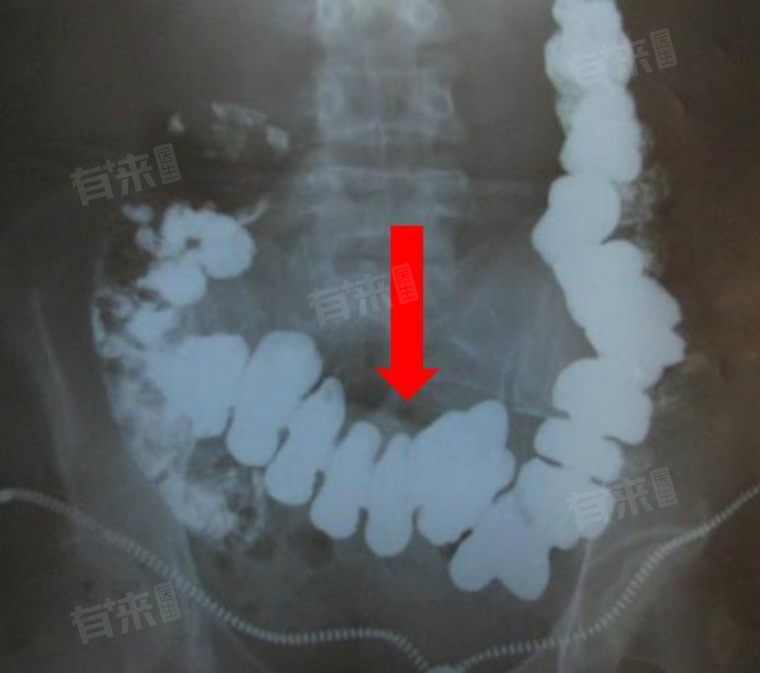

小肠下垂,医学上称为小肠脱垂,是指小肠的位置发生改变,脱离了正常的解剖位置,可能会对肠道功能产生不良影响。当出现小肠下垂时,注意治疗方法有一般治疗、手法复位等。